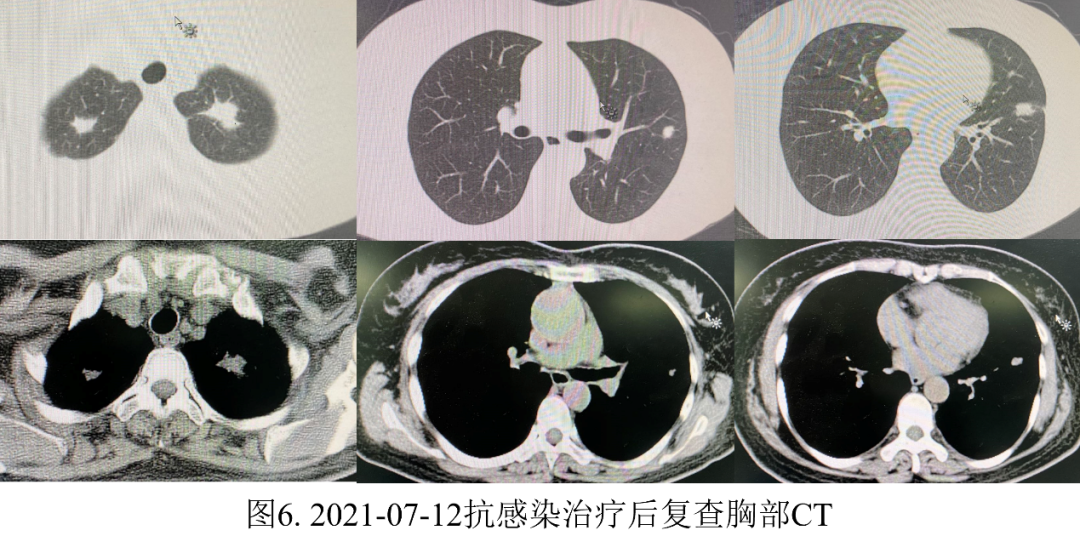

另外,生气的人更容易导致免疫功能低下,免疫功能受损,容易引起肺结节。那么中医如何解决这种“气怒”的肺结节人群呢?分享几个案例。案例1:马先生,65岁,吸烟30多年。2020年7月,因胸闷、胸痛、憋气等症状到医院就诊。CT检查后显示双肺多发结节。左肺下叶胸膜下有较大的实性结节,直径约6 mm,未给予其他治疗。